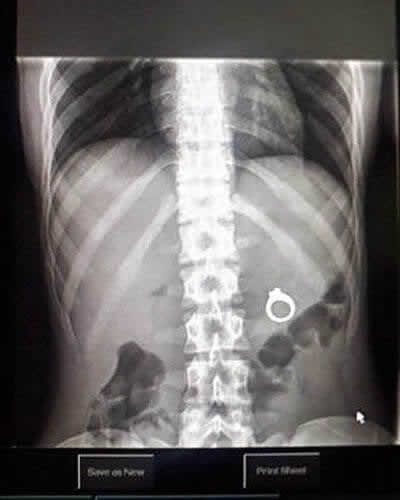

Les urgences sont toujours pleines de surprises. Les professionnels de la santé ont tout vu, et la machine à rayons X ne ment jamais. Il est vraiment choquant de voir ce que les gens parviennent à avaler ou à se coincer dans leur corps. Cette image montre une bague de fiançailles logée profondément à l’intérieur d’une patiente. Comment elle a fini près de ses organes internes est un mystère pour l’éternité !

Cela semble être une demande en mariage qui a mal tourné. Le partenaire a probablement caché le bijou dans une boisson ou un repas, et elle l’a avalé accidentellement. Espérons que les chirurgiens ont réussi à récupérer la gemme sans encombre !